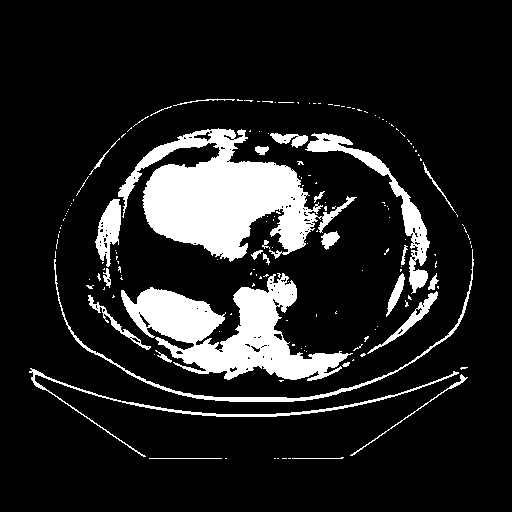

Reconstructed NATIVE CT scan (cycle consistency)

Full window (WL 1023.5, WW 4095 β†’ Low βˆ’1024, High +3071)

Actual HU range: [-1024.0, 3071.0]